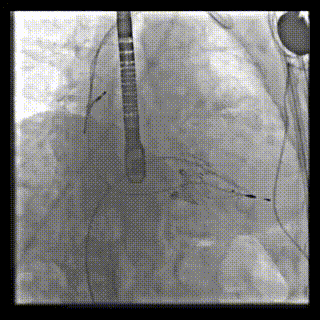

本周三例接受LuX-Valve Plus經(jīng)血管三尖瓣置換術(shù)的患者中,第一例患者為冠狀動(dòng)脈旁路移植術(shù)+Bentall+二尖瓣成形術(shù)后;第二例患者為永久起搏器植入術(shù)后,存在跨三尖瓣導(dǎo)線;第三例患者合并房顫、房缺及左心耳封堵術(shù)后。

三例患者入院后,葛均波院士團(tuán)隊(duì)周達(dá)新教授、潘文志教授、張?jiān)床┦俊㈥惿┦考靶某业呐舜湔浣淌?、李偉教授?duì)患者的情況進(jìn)行詳細(xì)評(píng)估和討論,最終決定為三例患者選擇LuX-Valve Plus40mm、50mm和50mm型號(hào)的瓣膜進(jìn)行手術(shù)治療。手術(shù)后即刻拔除氣管插管,術(shù)后患者三尖瓣反流癥狀得到顯著改善,復(fù)查心超結(jié)果顯示人工三尖瓣瓣膜支架固定穩(wěn)定,瓣葉關(guān)閉形態(tài)未見異常,未見明顯反流。